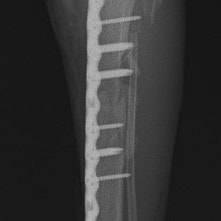

症例:交通事故による椎体脱臼

柴犬:9歳、避妊雌

交通事故直後、胸腰部に激しい疼痛、両後肢に完全麻痺を認め、シェフシェリントン徴候を呈していました。レントゲン検査において、第11-12胸椎間の脱臼が認められました。

脊髄の減圧、脊柱管の再構築・安定化を目的に、片側椎弓切除術およびMatrixMANDIBLE Plateによる椎体固定を実施しました。

隣接椎体を架橋するようにプレートを設置しました。

術後レントゲン写真